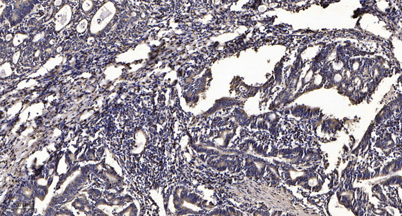

IF

IHC

Recomended Dilution Immunohistochemistry: 1/100 - 1/300. ELISA: 1/5000. Not yet tested in other applications.